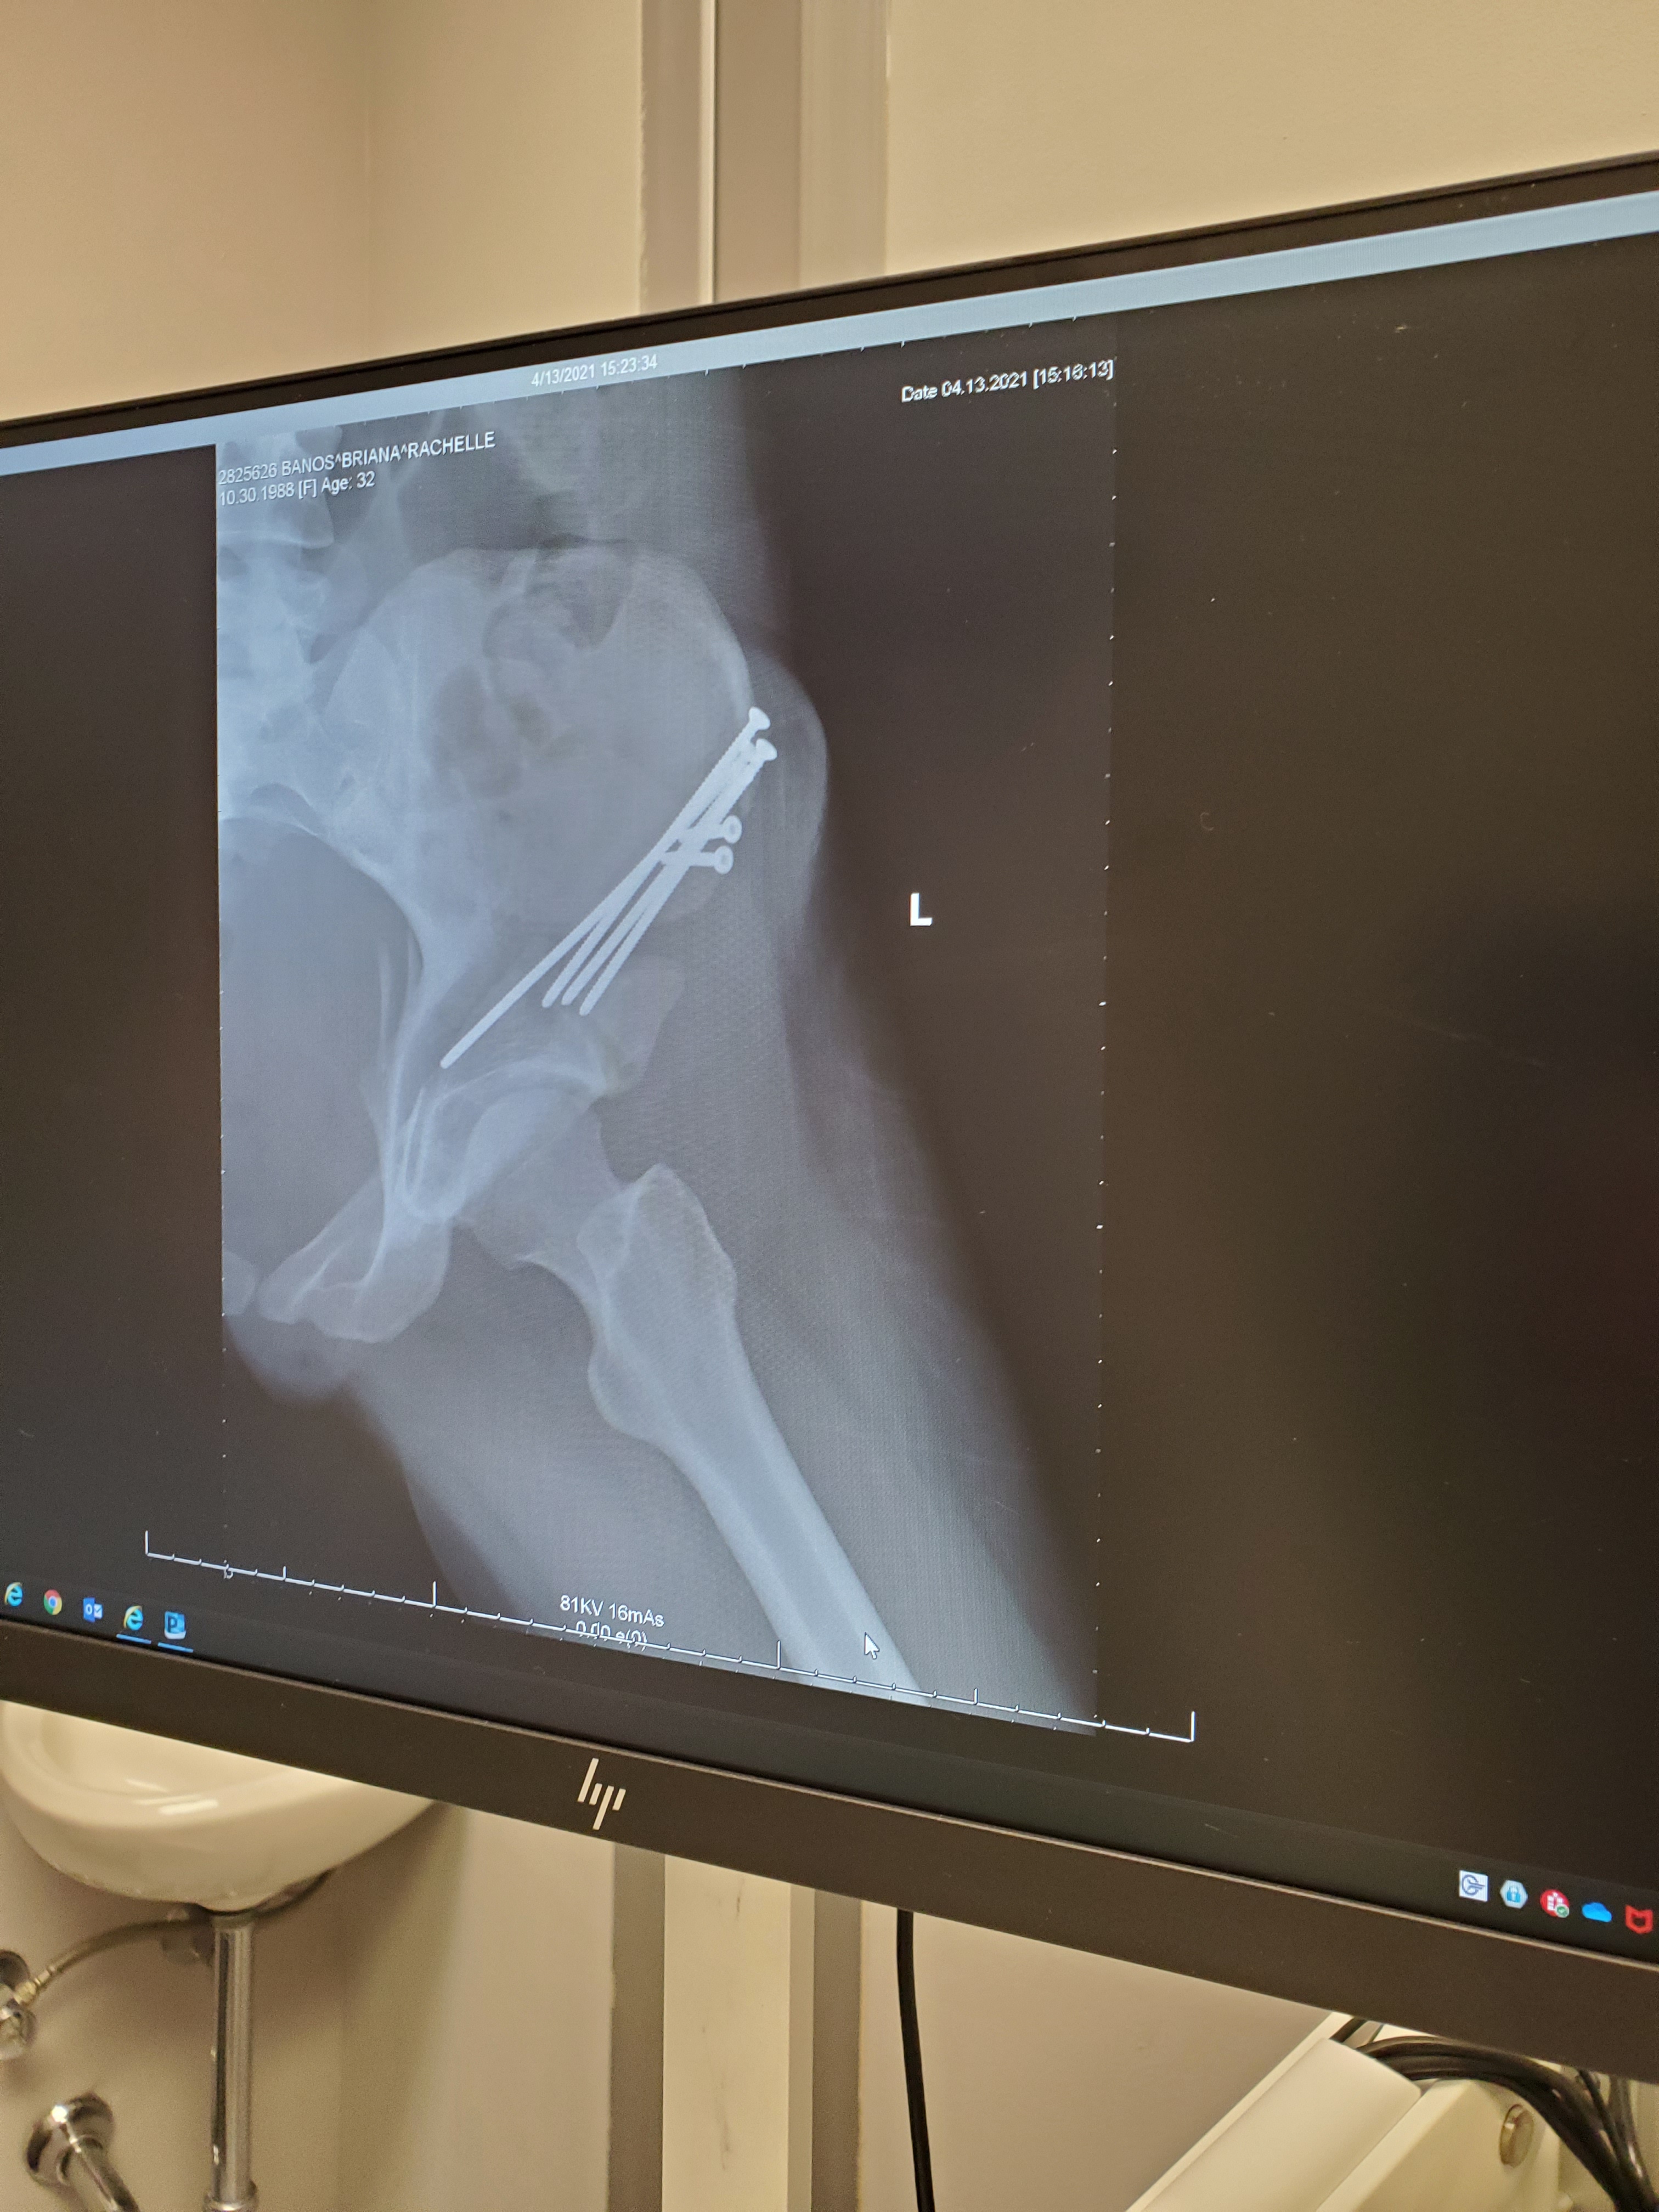

It’s now been 5 weeks since my first arthroscopy surgery and 3 weeks since my PAO surgery.

But let’s cut to the chase… who wants to see the money pics!! Screws and all!